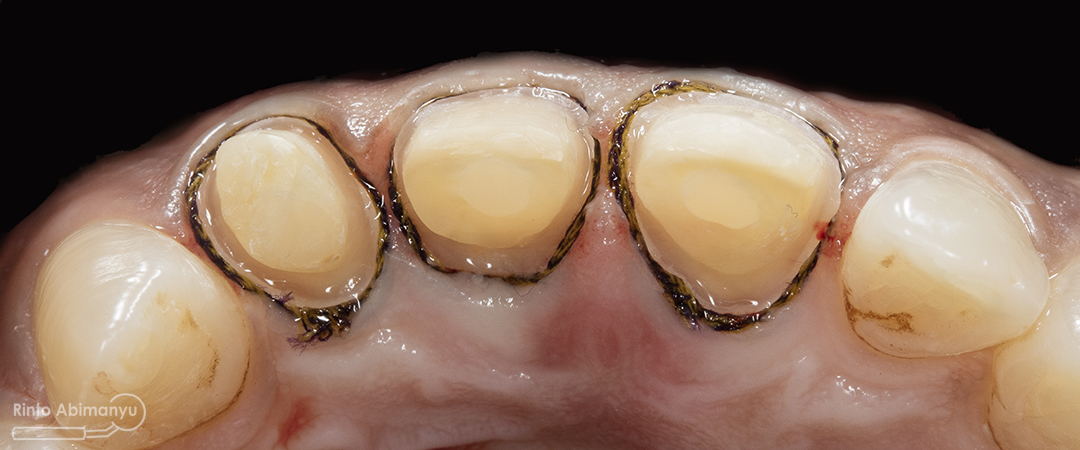

ini hasil preparasi gigi-giginya…

Hasil preparasi tampak depan